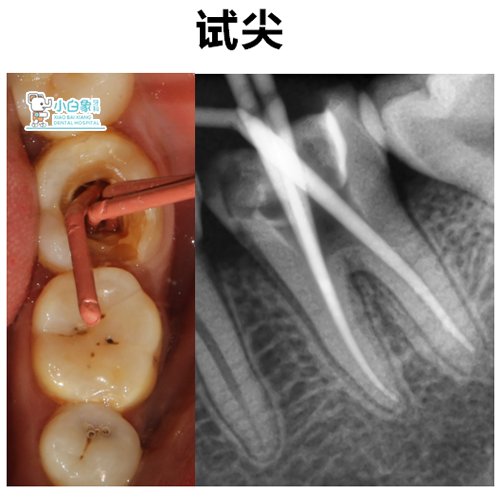

治疗过程:去除充填材料,清理根管,远中根长约19mm,近中18.5mm,扩至M2,荡洗,隔湿干燥,根充糊剂+牙胶尖根充,垫底,3MZ250充填,抛光。